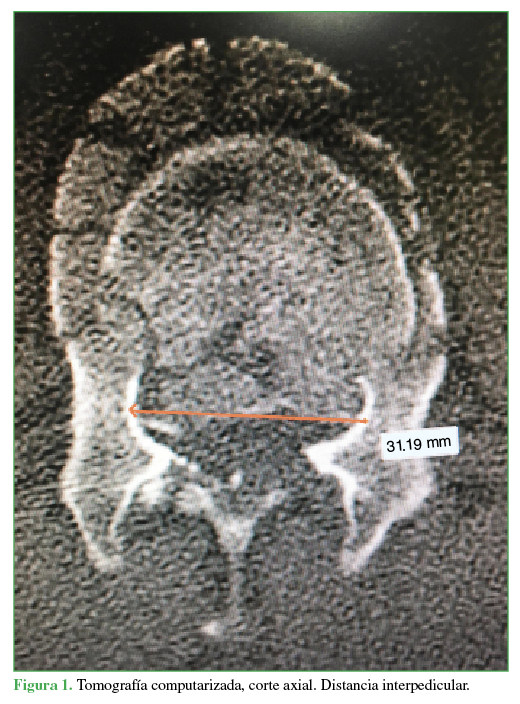

- Distancia interpedicular (distancia más amplia medida en milímetros entre ambos pedículos de la vértebra fracturada en el corte axial de TC) (Figura 1).

Distancia interpedicular.